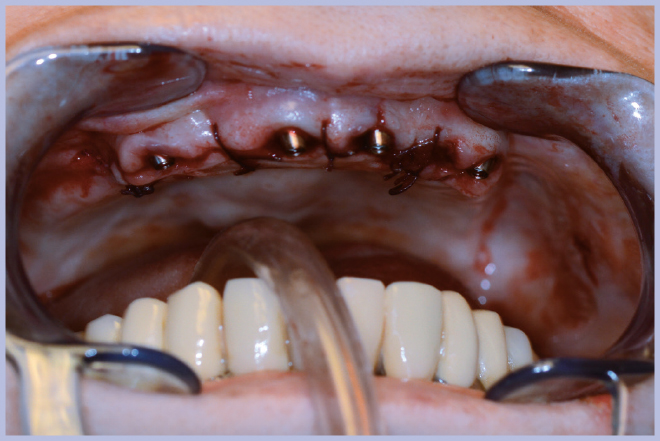

Dopo l’estrazione dei 3 elementi residui (Fig. 2), sono stati posizionati 4 impianti Max Stability Ø3,75 mm (2 di lunghezza 10 mm e 2 di lunghezza 12 mm).

Dopo il posizionamento implantare si sono utilizzati 4 monconi per protesi avvitata angolati a 25°. Dato che non si è utilizzato alcun modello in gesso ma si è lavorato direttamente in bocca, la procedura ottimale in questi casi è quella di rimuovere dai monconi gli esagoni Exacone® 360°.

Per la scelta dei monconi, in termini di altezza del tratto transmucoso e angolazione, si è utilizzato il kit di monconi di prova Standard-Large. Quindi si sono prelevati i monconi definitivi dal kit Leone All-on-Four/All-on-Six fornitoci in conto visione: questo servizio offerto dall’azienda ci consente di fare a meno di un magazzino dei componenti protesici, permettendone l’acquisto dopo aver già selezionato le misure di interesse.

Sui monconi, dopo aver attivato la connessione a cono Morse (Fig. 3), sono state fissate le apposite cappette in titanio con le viti a testa alta (Fig. 4) ed è stata realizzata un’armatura di rinforzo per mezzo di una sincristallizzatrice intra-orale. In particolare la barra è stata ottenuta mediante saldatura sulle cappette di un filo pre-modellato di titanio grado 2 (Figg. 5, 6).